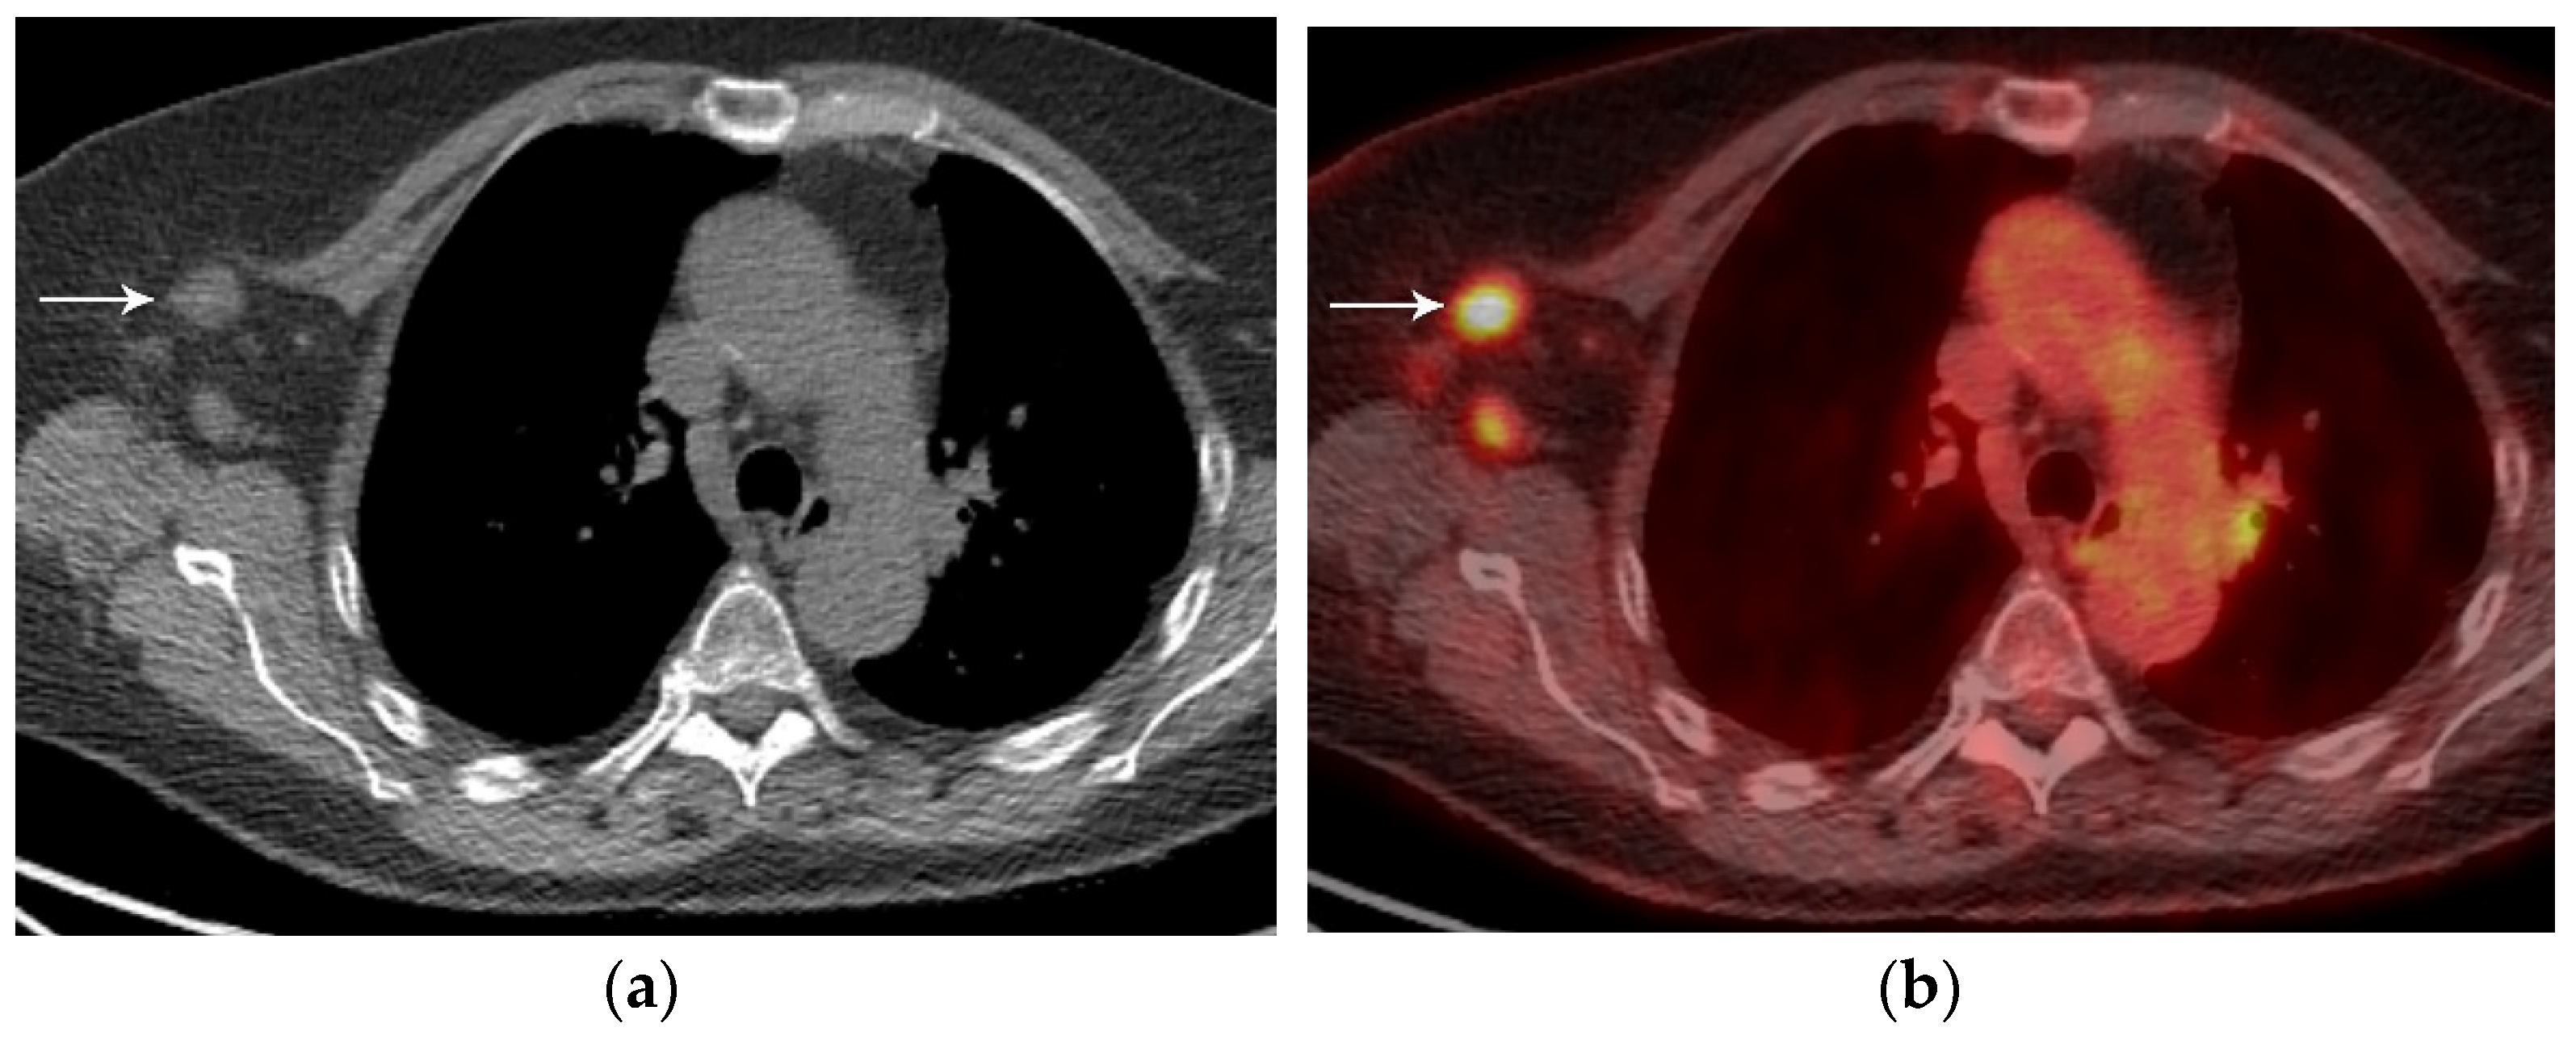

3. N Classification